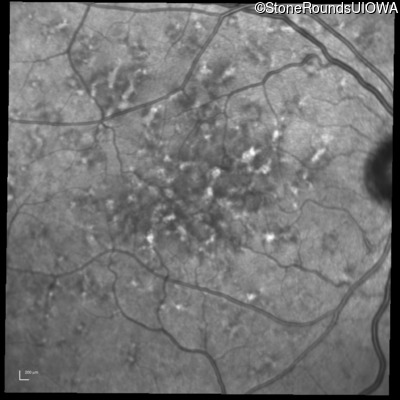

Fluorescein Angiography - Left - 20/40 +1 sc

Exemplar